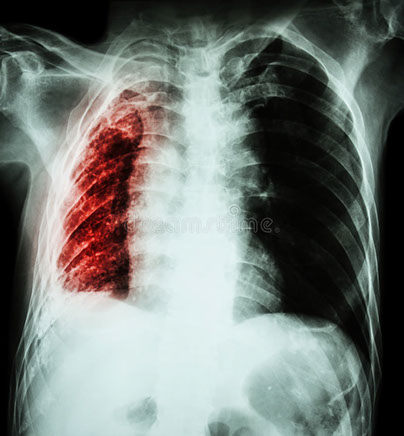

• Tuberculosis Pulmonar

La tuberculosis pulmonar es una enfermedad infecciosa causada por una bacteria llamada Mycobacterium tuberculosis que se puede adquirir por la inhalación de gotitas de agua provenientes de la tos o el estornudo de una persona infectada (el llamado bacilo de Koch).

Entre sus síntomas más frecuentes en un estado avanzado de la enfermedad se encuentran la fiebre, la sudoración, la pérdida de peso, el cansancio general, la tos, el dolor torácico, y el sangrado en esputo.

Para el diagnóstico es necesario realizar un aislamiento de estos bacilos, en cultivo de muestras de esputo o a través de diversas pruebas o biopsias (broncoescopia, biopsia pleural o biopsia glangionar).

Si no se realiza un tratamiento, la tuberculosis provoca la muerte. El tratamiento habitual se basa en la combinación de, como mínimo, cuatro fármacos (Isonizida, Rifampina, Pirazinamida y Etambutol) o en ocasiones otros, administrados varias veces al día durante un período de tiempo prolongado (seis meses, por lo general).

Dado que es una enfermedad contagiosa, se deben seguir los consejos médicos en lo que respecta al control de la medicación y al aislamiento inicial para evitar una posible extensión de la enfermedad al resto de la población.